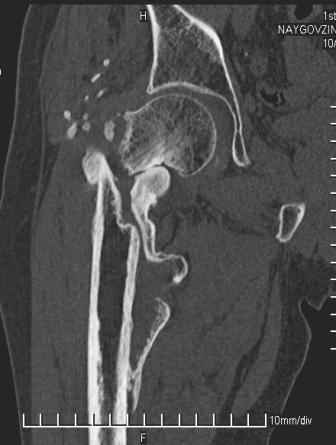

Уважаемый Глеб! Укорочение наверное побольше, да и наружно-ротационная установка скорее всего присутствует. Суставная щель прекрасная, головка живее всех живых. Ратую за подвертельную с латерализацией: исключает нарушение механической оси («исключает вальгус в коленe»), максимально удлиняет без натяжения m.iliacus. Для иллюстрации остеотомия-переделка (слава богу не автопеределка) у мужчины 65 лет.

Филипчук.

PS. Извините за качество последнего снимка, рентгенограмма выполнена по м. жительства, там где был проведен синтез. Последний снимок выполнен через 2 мес. п\о, больной без разрешения начал наступать, слава богу все обошлось.